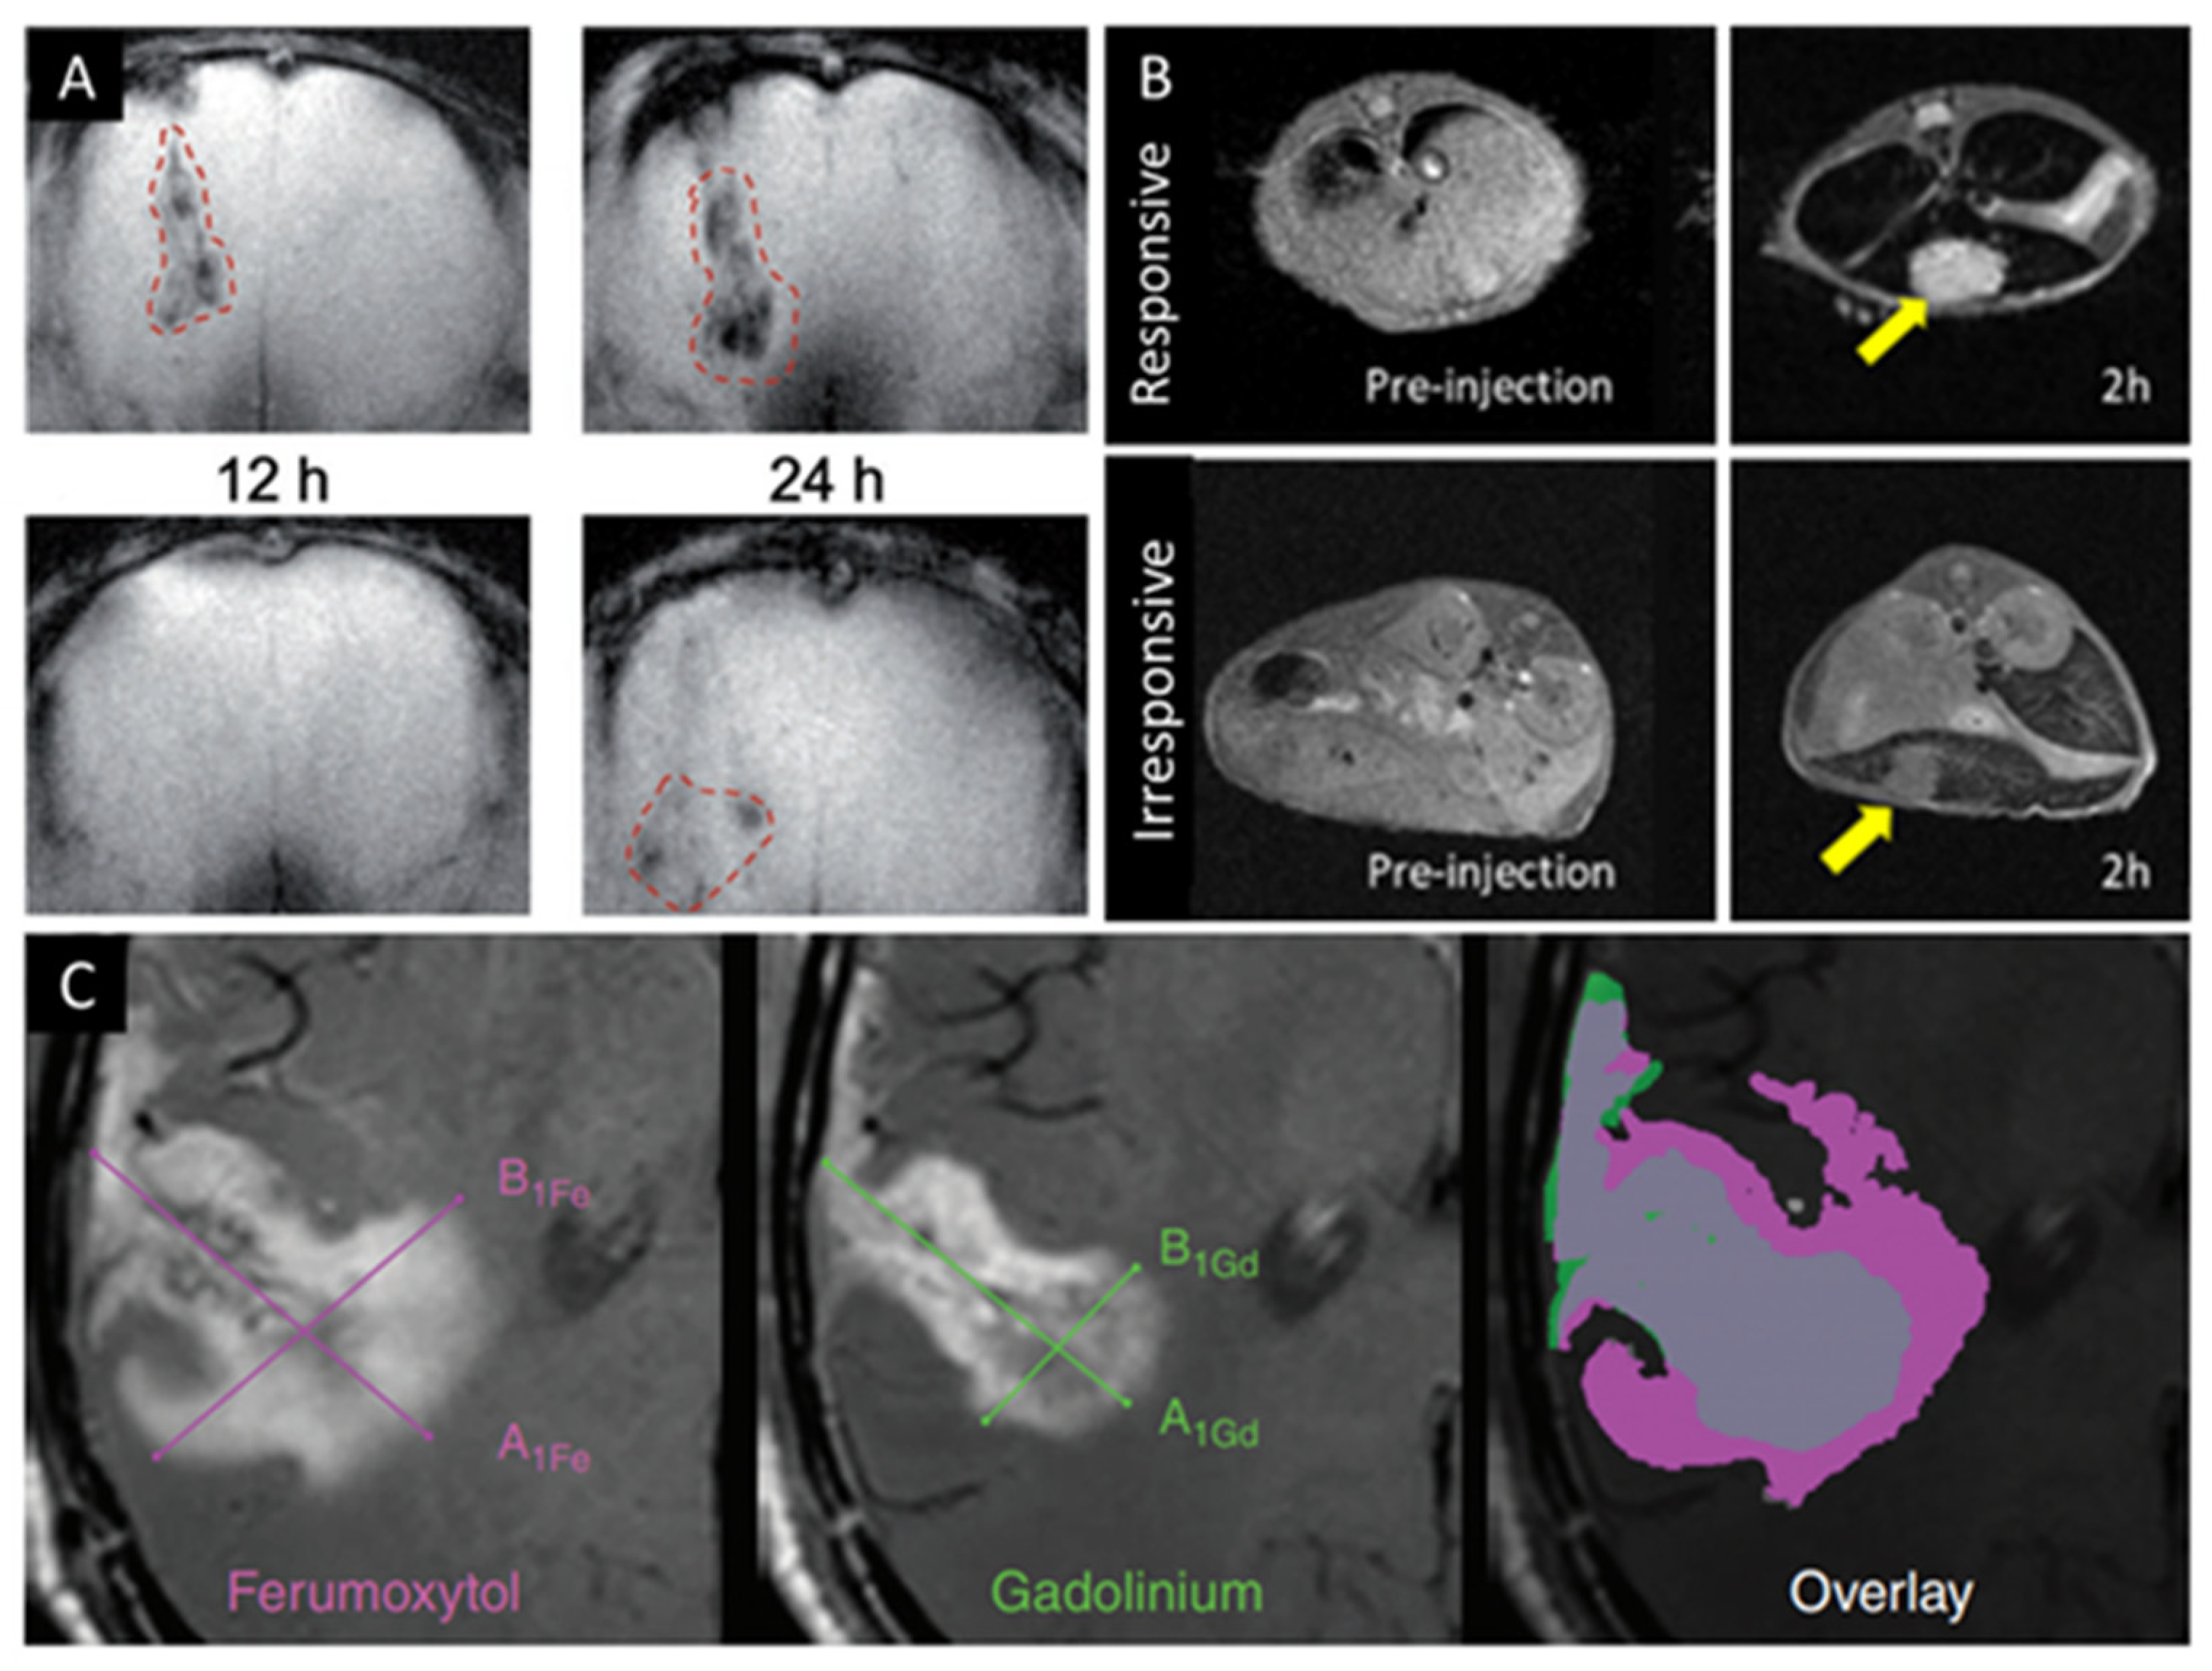

- Barajas, R.F.; Hamilton, B.E.; Schwartz, D.; McConnell, H.; Pettersson, D.R.; Horvath, A.; Szidonya, L.; Varallyay, C.G.; Firkins, J.; Jaboin, J.J.; et al. Combined iron oxide nanoparticle ferumoxytol and gadolinium contrast enhanced MRI define glioblastoma pseudoprogression. Neuro-Oncology 2019, 21, 517–526. [Google Scholar] [CrossRef]

- Zhu, X.; Li, J.; Peng, P.; Hosseini-Nassab, N.; Smith, B.R. Quantitative Drug Release Monitoring in Tumors of Living Subjects by Magnetic Particle Imaging Nanocomposite. Nano Lett. 2019, 19, 6725–6733. [Google Scholar] [CrossRef]